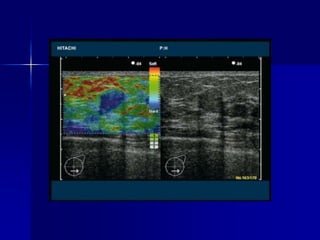

 Ultrasonido

 Elastografía

Métodos de Imagen Ultrasonido  Elastografía  Mamografía  Resonancia magnética